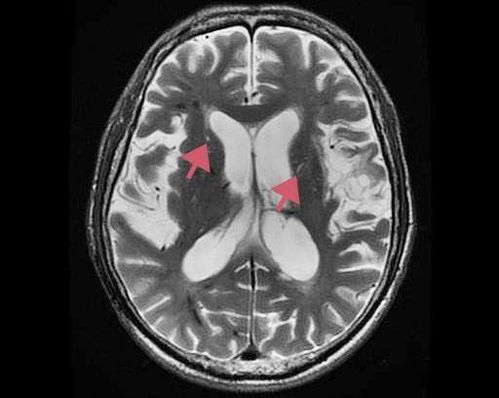

脑出血片子图片解析

脑出血片子图片解析,脑出血检查报告单图片

脑出血|征象

患者:巴德尔苏德,男,57岁,右侧颞顶枕叶脑出血,呈昏睡

丘脑出血